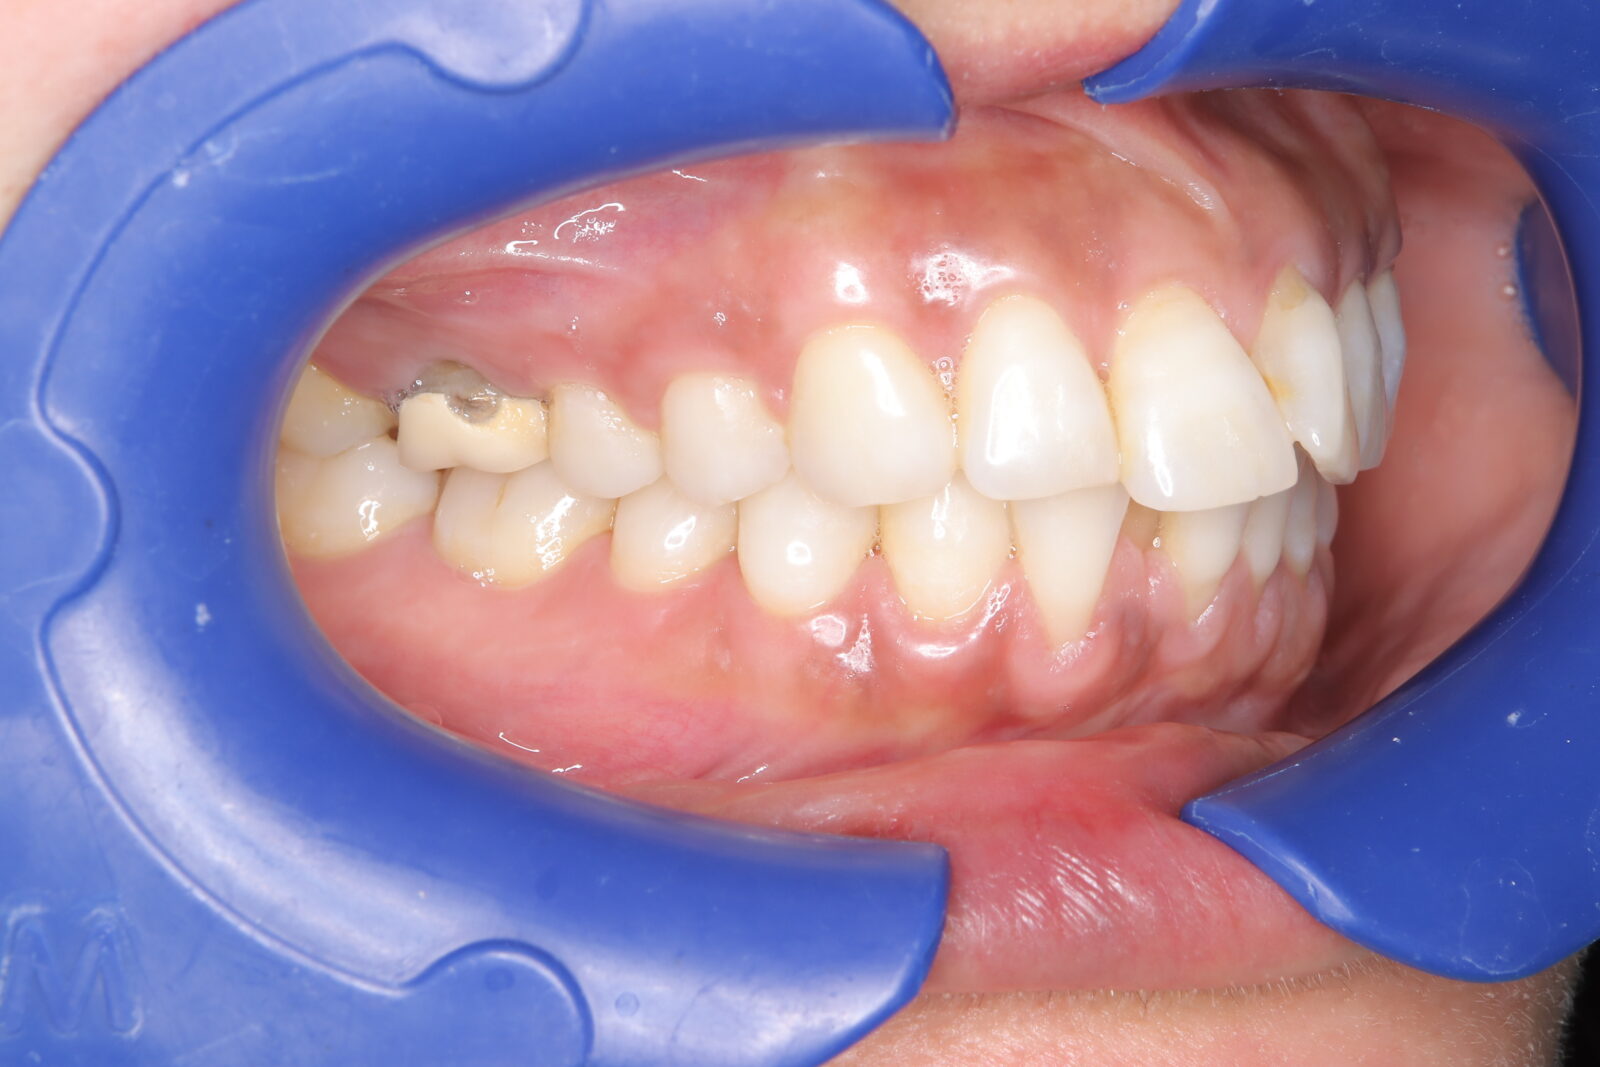

インビザライン(全体矯正)+ホワイトニングコース+セラミック治療の症例

過去にワイヤー矯正で治せなかったクロスバイト。インビザライン(全体矯正)とホワイトニングとセラミック治療で綺麗な笑顔へ。

・費用:726,000円(税込) ※ホームホワイトニングと右上6番ジルコニアクラウン含む

・治療期間:15ヶ月

・通院回数:10回

・32歳女性

-リスクと副作用-

・長時間マウスピースを装着するため、むし歯や歯周病のリスクがある。治療後はリテーナーを装着しないと後戻りしてしまうリスクがある。

・ホワイトニング剤の影響で知覚過敏が起こる可能性がある。色が徐々に戻る可能性がる。

・セラミック:過度な衝撃によって割れることがある。